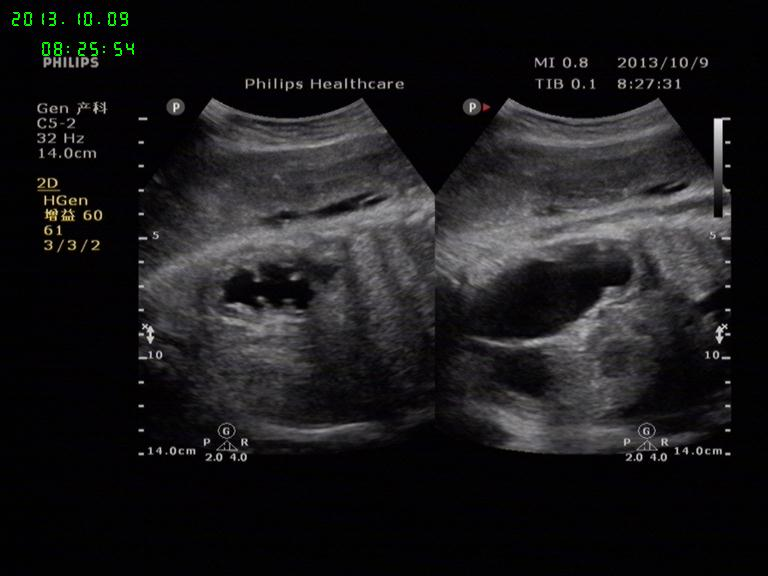

胎儿左肾积水

孕38周胎儿,左肾积水,右肾大小形态正常,羊水量AFI:20.5cm

不错,学习了!怎么打出胎儿肾标准切面